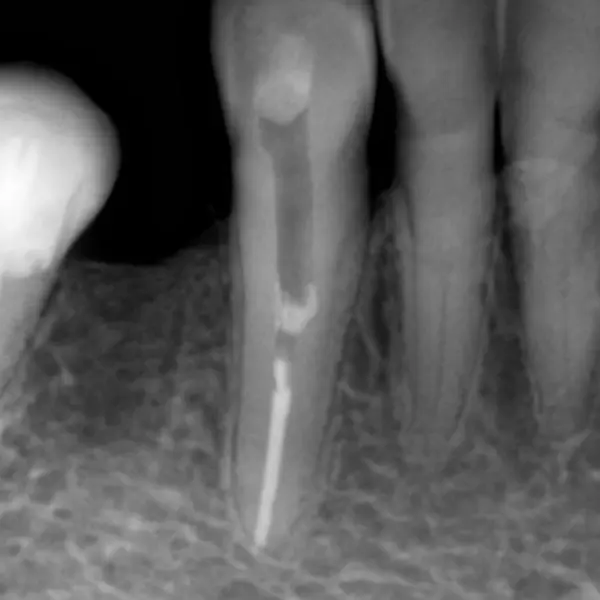

Формирование канала:

- Машинный файл 35.04: этот инструмент был использован для формирования стабильного и предсказуемого конуса основного канала.